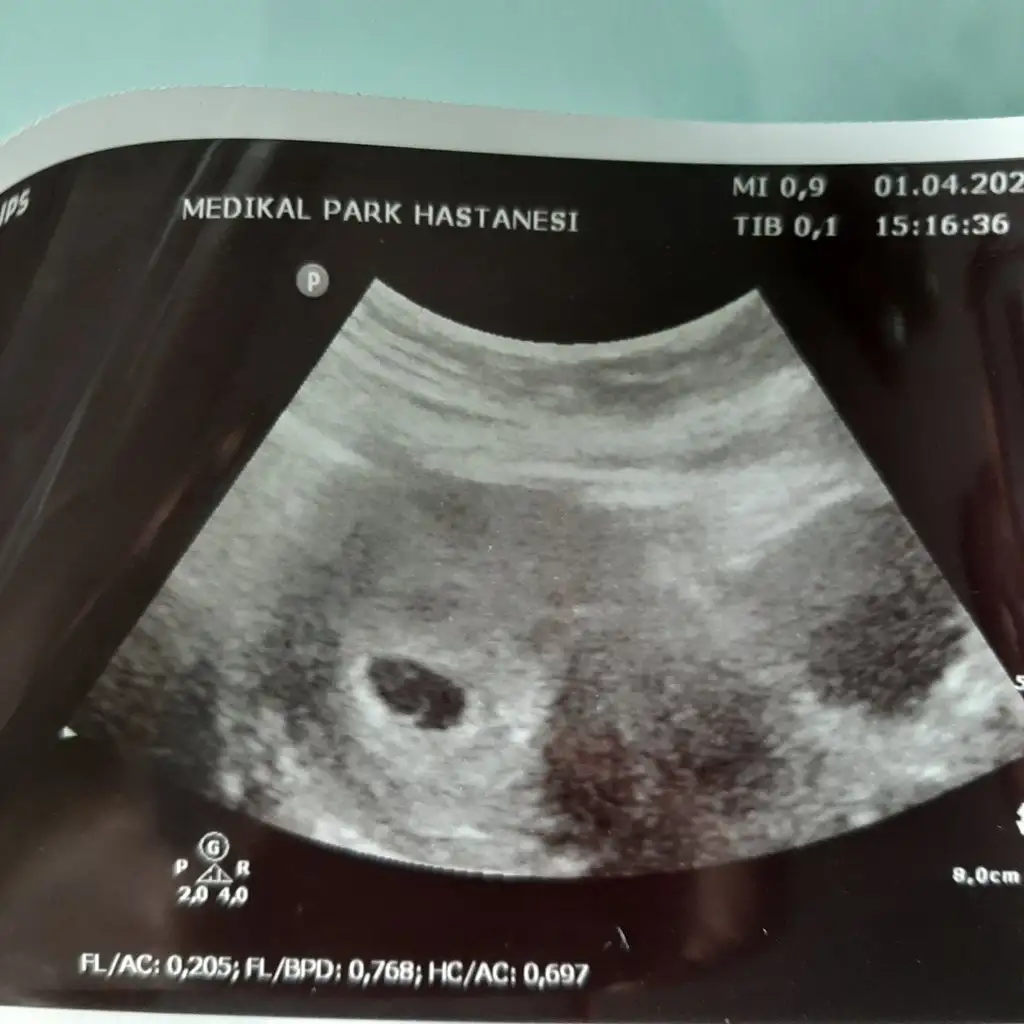

Ben şimdilik tahmininizin kısmen tuttuğunu söylemek için yazdım özellikle.. ultrason fotosunu da ekliyim 12.hafta içinde nub teoremiyle tahminlerinizi alıyım böylece birlikte teyit etmiş olalım şimdiden teşekkür ediyorum :)

Aynen nubu dik erkek 😊 kesinleşince anketimi oylarsanız sevinirim 😊